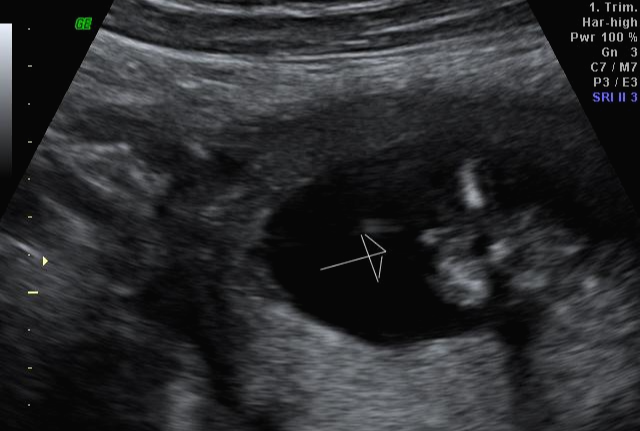

한 달 뒤인 17차 때 다시 사설로 가서 초음파 검사를 받았는데 검사해주시는 분 께서 한참을 보시더라고요~ 그러면서 어떻게 보면 딸 같다고 하셔서... 응? 100프로 아들이라 해서... 다 아들껄로 준비하고 있는데.. 무슨 소리지? 하고 다시 한번 봐달라고 하니 아들이라 하시면서 위에 초음파를 보여주셨어요!

한데 기분이 참 찝찝했어요~ 뭔가 숨기고 있는 듯한.. 정확하지 않는 듯한 느낌 ㅋㅋㅋ... 그래서 임신 17주 차부터 아이 용품 구매하는 걸 중단하고 병원에서 20주 차 정밀 초음파 검사를 기다려 보기로... 가족도 다 아들로 알고 있고 벌써 아들 꺼 처럼 보이는 용품들로 준비했기 때문에 성별 반전이 없기를 기대했어요 ㅠㅠ